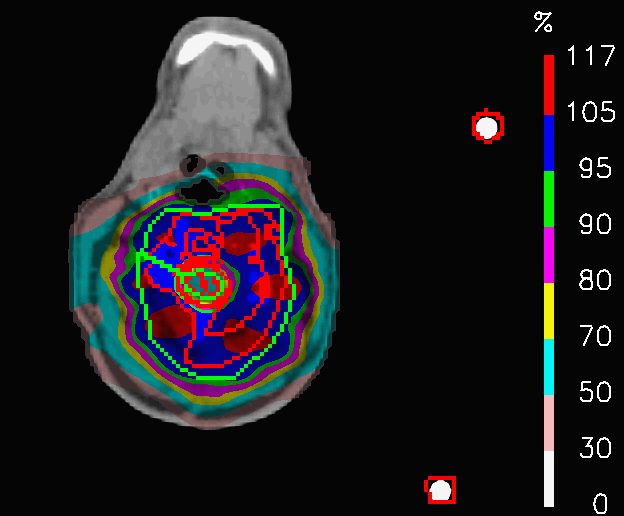

One common indication for proton therapy centers is represented by tumours extending both in the head and neck. As the tumour extends over a relatively big area, the treatment can result rather toxic for many organs at risk. These cases are usually treated with four fields, as shown in Fig.5: two coming from the front, aimed at covering the target volume at the level of the shoulders, two coming from behind, supposed to deliver the dose in the head part of the tumour. The drawback of this geometry is that, despite the dose constraints, the front fields irradiate OARs inside the head and, in the same way, the back fields release high dose to the shoulders, without being crucial for target coverage in that point.

The OL penalization is, here, exploited to switch off the fields in selected areas and to test a new field geometry. In PLAN-OL-1, two artificial VOIs were drawn at the level if the shoulders and were assigned with OL = 1, to switch off, respectively, the posterior fields irradiating that area. In PLAN-OL-2, two addional artificial VOIs are created at the level of the head and set with OL = 1, to switch off the anteriori fields in the part of the patient volume and a fifth intra-cranial field is added to compensate for the target coverage, as shown in Fig.6.

Refer to caption

Figure 6: Head and neck tumour: azimuthal CT slice showing the fifth intracranial field added for PLAN-OL-2.

In PLAN-OL-2, a different field geometry has been investigated: the posterior fields are switched off at the level of the shoulders, the anterior ones at the level of the head and a fifth intracranial field is added (Fig.6). The goal was to achieve a better preservation of the OARs inside the head. The dose distributions (Fig.16) share a very similar coverage of the target volume, but they are characterized by substantial differences in the dose delivered to the OARs, as shown by Table 5. In fact, the huge improvements in the sparing of the chiasm, right lens (Fig.17a), left lens (17b), left inner ear and the spinal cord (considering in first place the decrease of 𝐃𝐦𝐚𝐱subscript𝐃𝐦𝐚𝐱\mathbf{D_{max}}) are followed by a significant increase of the peak dose inside the thyroid and the mean dose to the brainstem. In this case, PLAN-OL-2 is not necessarily superior to PLAN-NOM, but it is undeniable that the OL penalization has allowed the planner to test a scenario, that the simple enforcement of the dose constraints would not have provided.